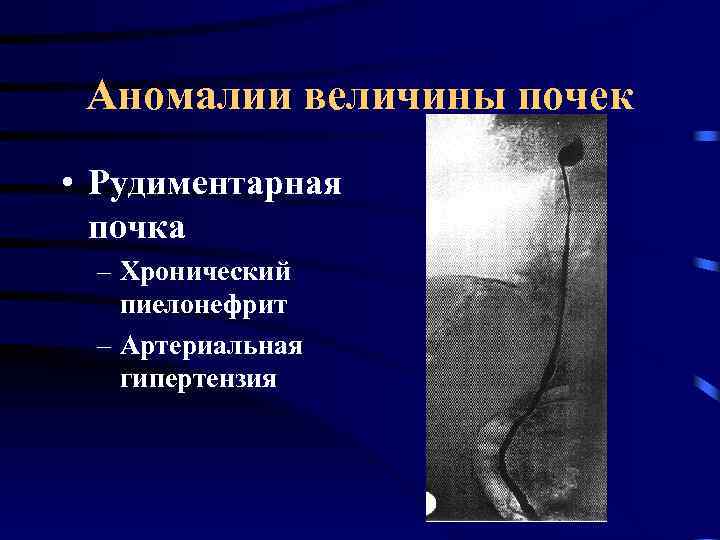

Аномалии величины почек • Рудиментарная почка – Хронический пиелонефрит – Артериальная гипертензия

Аномалии величины почек • Рудиментарная почка – Хронический пиелонефрит – Артериальная гипертензия